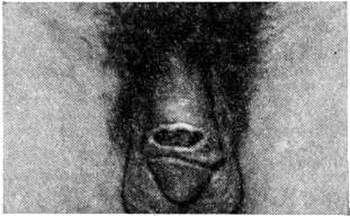

Клиническая картина. Инкубационный период 1½ — 2 недели. В типичных случаях заболевания различают три последовательных периода. Первичный (лимфогранулематозный шанкр): на месте внедрения возбудителя, то есть в области половых органов (возможно экстрагенитальное поражение — губы, полость рта, язык и другие), возникает единичный пузырёк (реже папула), быстро трансформирующийся в эрозию, а затем в язву диаметром до 1—3 см неправильных округлых или овальных очертаний, неглубокую, с неровным дном (рисунок 3), покрытую гноем серовато-тусклого, иногда желтовато-зеленоватого оттенка. Типично наличие островоспалительного ободка и отсутствие характерного для твёрдого шанкра (смотри полный свод знаний Сифилис) уплотнения в основании. Обычно через 7—9 дней на фоне намечающейся тенденции язвы к самопроизвольному заживлению наблюдается постепенное увеличение, уплотнение и болезненность регионарных лимфатических, узлов (у мужчин чаще паховых, у женщин — малого таза). Спустя 1½—2 месяцев после заражения в результате генерализации процесса наступает вторичный период: лимфатических, узлы увеличиваются ещё больше, уплотняются и в результате распространения воспалительного инфильтрата (периаденита) сливаются между собой в массивный с бугристой поверхностью болезненный при пальпации конгломерат. В дальнейшем в толще конгломерата развиваются многочисленные очаги размягчения, свищи и фистулы, из которых выделяется гной, иногда с примесью крови. При торпидном течении процесса выражены склеротические изменения поражённых тканей, формирование спаек и рубцов, что приводит к лимфостазу (смотри полный свод знаний) и Отёкам в области половых органов. Во вторичном периоде Лимфогранулематоз паховый, кроме поражения регионарных лимфатических, узлов, в патологический процесс могут быть вовлечены глубокие лимфатических, узлы малого таза, возможно метастазирование инфекции из области гениталий в отдаленные от первичного очага поражения участки (метастатические бубоны верхних конечностей), поражение внутренних органов, суставов, вен (флебит бедренных вен), а также эпидидимит, аднексит, ирит, конъюнктивит, кератит и даже менингит. Описаны случаи появления на коже больных Лимфогранулематоз паховый высыпаний аллергического характера, напоминающих крапивницу, узловатую или многоформную экссудативную эритему, сыпь при скарлатине. Третичный период заболевания обычно проявляется через 1½— 2 года (иногда несколько позже) и выражается главным образом в развитии так называемый генитоаноректального синдрома — тяжёлого фистулезно-спаечного процесса, развивающегося в результате распространения воспалительного процесса на промежность и перианальную область с развитием проктита (смотри полный свод знаний) и парапроктита (смотри полный свод знаний). Наиболее ранний признак генитоаноректального синдрома — тянущие боли в области промежности, скудные сукровично-гнойные выделения из ануса. При ректороманоскопии — отёк и гиперемия, особенно нижнего отдела прямой кишки, эрозии с сукровично-гнойным отделяемым, кровоточивость и болезненность при малейшем растяжении слизистой оболочки. Рубцово-склеротические изменения в прямой кишке приводят к развитию стриктур, охватывающих обычно кольцевидно прямую кишку, что может привести к почти полному закрытию просвета кишки. Проктит и парапроктит могут сопровождаться абсцедированием с последующим изъязвлением, образованием свищей в области заднего прохода, промежности, половых органов и другие. У женщин язвенный распад и последующее рубцевание очагов поражения нередко приводят к стриктурам влагалища, особенно в области входа, значительным деформациям малых и больших половых губ, клитора. В третичном, реже во вторичном, периоде заболевания возможны общие явления: слабость, потеря аппетита, головные боли, похудание, а также боли в суставах (поздний лимфогранулематозный полиартрит), ускорение РОЭ, лейкоцитоз анемия. Диагноз ставится на основании клинические, данных, характерных для каждого периода заболевания. Кроме того, диагноз Лимфогранулематоз паховый может быть подтверждён лабораторный данными: обнаружение возбудителя в мазках-отпечатках содержимого бубонов, выделение его при посевах в развивающихся куриных эмбрионах и культурах клеток, выявление группоспецифических комплементсвязывающих и типоспецифических флюоресцирующих антител, гиперчувствительности замедленного типа с помощью внутрикожной пробы (реакция Фрея). Аллерген для реакции Фрея готовят из гноя бубонов или из желточных культур возбудителя Лимфогранулематоз паховый, очищенных дифференциальным центрифугированием. По 0,1 миллилитров специфического и контрольного (не содержащего возбудителя Лимфогранулематоз паховый) антигенов внутрикожно вводят в сгибательные поверхности предплечий. Результат учитывают через 48 часов Реакцию оценивают как положительную при появлении папулы или уплотнения диаметром 5 миллиметров и более и при отсутствии уплотнения в месте введения контрольного антигена. Размер окружающей эритемы не учитывают. РСК и реакция Фрея при Лимфогранулематоз паховый подтверждает клинические, диагноз до 75% случаев. Формоловая реакция Гате—Папакостаса, ранее применявшаяся для подтверждения клинические, диагноза, не обладает специфичностью. Комплексная лабораторный диагностика позволяет выявить и латентные формы инфекции. Дифференциальный диагноз проводят с сифилисом (смотри полный свод знаний), мягким шанкром (смотри полный свод знаний), лимфоретикулезом, так называемый болезнью кошачьих царапин (смотри полный свод знаний Фелиноз). Лечение. Применяют сульфаниламиды (норсульфазол, сульфадимезин и другие) по 1,5 грамм 3 раза в день в течение 2 недель, а затем по 1,0 грамм 3 раза в день в течение 3 недель Курс лечения — 5 недель. При наличии глубоких фиброзных изменений, и в частности стриктур, через 2 недель показано назначение повторного курса лечения. Эффективны антибиотики тетрациклинового ряда (тетрациклин, окситетрациклин), а также эритромицин, олеандомицин и левомицетин. При присоединении вторичной стафилококковой инфекции показаны антибиотики пенициллиновой группы, устойчивые к пенициллазе (оксациллин, метициллин). Если имеются свищи, уродующие рубцы, стриктуры, показано применение алоэ, стекловидного тела, лидазы, бужирование уретры, при отсутствии эффекта — оперативное вмешательство. Прогноз в отношении жизни обычно благоприятный. Заболевание оставляет стойкий иммунитет и достоверных случаев повторного заражения не описано. В запущенных случаях возможны вторичная анемия, истощение, сепсис с летальным исходом. Профилактика: раннее выявление и санация источников заражения, контроль за полнотой и качеством лечения; лицам, имевшим половой контакт с больным Лимфогранулематоз паховый, с превентивной целью может быть проведена антибиотикотерапия (тетрациклин в течение 2 недель).